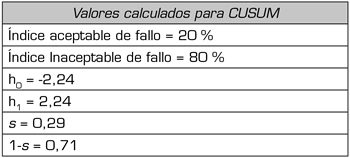

El tipo de test propuesto en nuestro estudio se aplica a conjuntos de datos discretos que toman valores binarios de acuerdo a la ocurrencia o no de un evento (en este caso éxito o fallo de la técnica) y que son recogidos en forma secuencial. La fórmula utilizada en el cálculo del CUSUM se muestra en la Tabla I. La función que define la curva de Cusum en la curva de rendimiento se calcula a partir de las constantes: porcentaje de fallo aceptable (p0) e inaceptable (p1), probabilidad de error Tipo I y II (α y β) a partir de los cuales se calcula el valor de s y los límites de decisión para la hipótesis nula y alternativa h0 y h1 que se mantienen constantes para cualquier valor de la muestra (Tabla I y II). Se tomó como porcentaje de fallo aceptable un 20 % e inaceptable de fallo de 40 % (Tabla II). El error α y β se tomó como 0,1.

Tabla II. Variables que se utilizan para el cálculo de las bandas de decisión (h0 y h1) y el valor de s a partir de los índices aceptables e inaceptables de fallo (p0 y p1) y el error tipo I y II (α y β)

Para cada éxito el valor de s se resta al valor de CUSUM previo y para cada fallo el valor de 1-s se suma al valor previo, por lo cual este aumenta con los sucesivos fallos, indicando el ascenso de la curva una tendencia al fracaso y desciende con los éxitos indicando un desempeño óptimo.

Cuando la curva de CUSUM cruza la línea de decisión h0 el porcentaje de fallo no diferirá estadísticamente de la frecuencia aceptable de este, por lo que se acepta la hipótesis nula con un error tipo II igual a β. Si la curva cruza la línea de decisión h1 entonces el porcentaje de fallo verdadero es significativamente más alto que el porcentaje de fallo aceptable (h1) con un error tipo I igual a α. Mientras no se alcance ninguno de los dos niveles de decisión no puede hacerse ninguna inferencia estadística que permita conclusión alguna y debe analizarse un número mayor de observaciones.